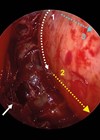

Transnasal endoscopic orbital decompression

Surgery for the eye complications of Grave’s disease is an area that, over the years, ENT has become more and more involved in due to our ability to access the orbit endoscopically. In this article, the authors describe their technique...